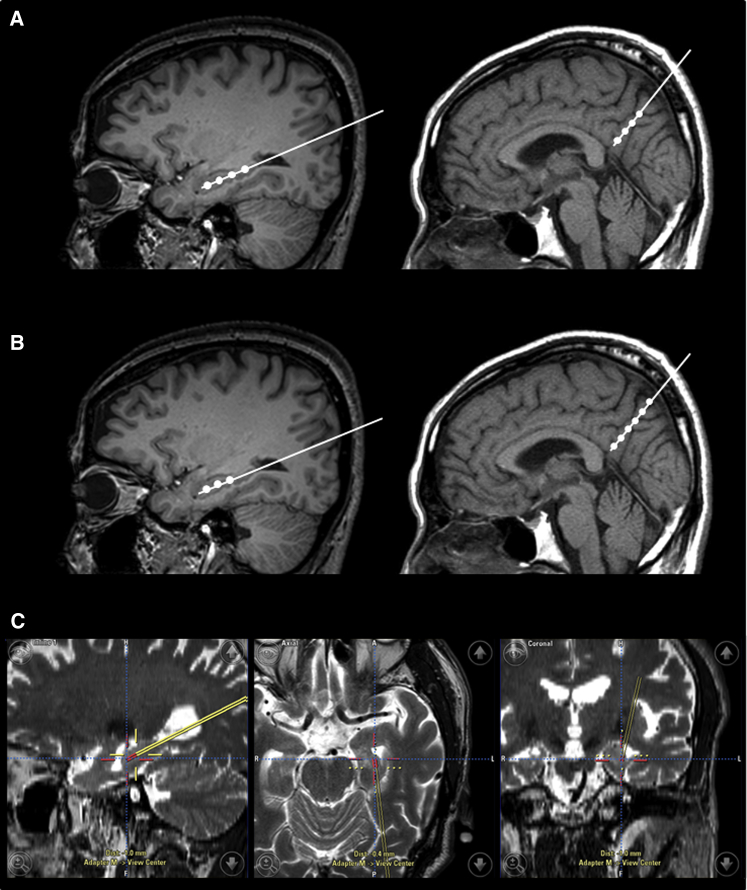

臍帶間充質(zhì)干細(xì)胞的立體定向給藥

- (A)術(shù)中導(dǎo)航引導(dǎo) hUCB-MSC 立體定向給藥。在縮回套管的同時,沿插入軌跡將 hUCB-MSC 注射到左右海馬和右楔前葉的四個部位(間隔 5 毫米)

- (B)然而,在九名患者中,有六名患者的第四次注射位于側(cè)腦室顳角,這可能是由于海馬嚴(yán)重萎縮所致。在這些情況下,省略的劑量被注射到右楔前葉,導(dǎo)致每個海馬有三個注射部位,右楔前葉有六個注射部位。

- (C)將 hUCB-MSC 立體定向注射到左海馬的示例